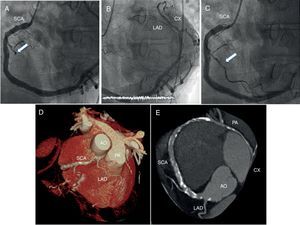

On coronary angiography, a single coronary artery (SCA) originating from the right coronary sinus was observed, which also supplied the territory of the left anterior descending (LAD) and circumflex (CX) arteries (Figure 1A and B; videos 1 and 2). An acute marginal branch had a thrombotic occlusion (Figure 1A; arrow). The acute occlusion was easily crossed with a Runthrough NS® floppy guidewire. Thromboaspiration was attempted but it was impossible to advance the aspiration catheter due to the diffuse disease of the vessel. Simple angioplasty with a semicompliant balloon (2 mm×15 mm) was therefore performed, with recovery of TIMI 3 distal flow (Figure 1C; arrow). We decided not to implant a stent because of diffuse disease and the small diameter of the vessel.

(A and B) Coronary angiography showing a single coronary artery (SCA) originating from the right coronary sinus, also supplying the territory of the left anterior descending (LAD) and circumflex (CX) arteries, and thrombotic occlusion of an acute marginal branch (A, arrow); (C) primary percutaneous coronary intervention recovering distal TIMI 3 flow in the culprit vessel (arrow); (D and E) multislice computed tomography reconstruction. After its origin, the main trunk of the SCA crosses the base of the heart to supply the contralateral coronary artery. Immediately after the origin of this main trunk, it also gives off a small vessel that reaches the anterior interventricular sulcus anteriorly to the aorta (AO) and pulmonary artery (PA) to supply the proximal LAD territory.

The patient evolved well and was promptly extubated. In order to confirm the origin and course of the SCA, multislice computed tomography (MSCT) was performed. It confirmed the existence of an SCA originating from the right sinus. Immediately after the origin of this main trunk, it gave off a small vessel that reached the anterior interventricular sulcus anteriorly to the aorta and pulmonary artery (proximal LAD territory) (Figure 1D). The single common trunk, 7 mm in diameter at its proximal segment, had numerous calcified plaques along its route without significant stenosis. A large left posterolateral branch followed the left atrioventricular groove supplying the nominal CX territory (Figure 1E). Finally, the SCA gave rise to a distal branch on the distal anterior wall of the left ventricle, completing the irrigation of the LAD territory. Given these findings, the SCA was classified as RII-A subtype according to Lipton's classification. Due to the non-malignant course of the SCA, the patient was discharged under medical therapy consisting of dual antiplatelet therapy (aspirin and clopidogrel) for 12 months, atorvastatin, metoprolol and enalapril. After one year of clinical follow-up, he remains asymptomatic, with no further adverse events.